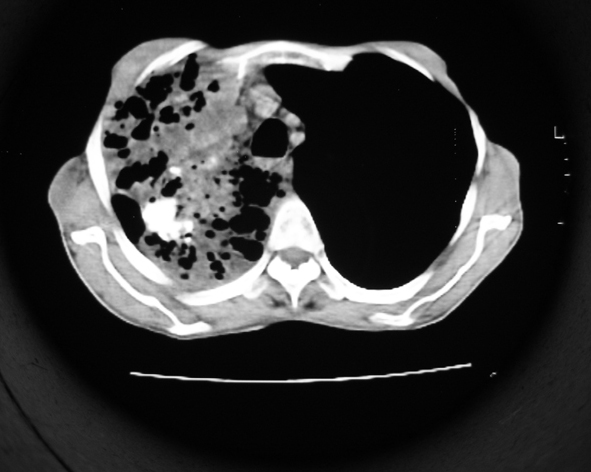

男53岁,咳嗽气短,以往身体健康.

右肺上叶多发多形态空洞及增殖灶,可见团块钙化,胸膜肥厚、粘连,考虑继发型肺结核可能性大

1.右肺上叶干酪性肺炎,2。肺气肿,肺大泡

右肺上中叶结核干酪性肺炎

右肺中上叶干酪性肺炎。

支持右上肺继发性肺结核并干酪性肺炎,右肺大泡,左肺代偿性气肿。